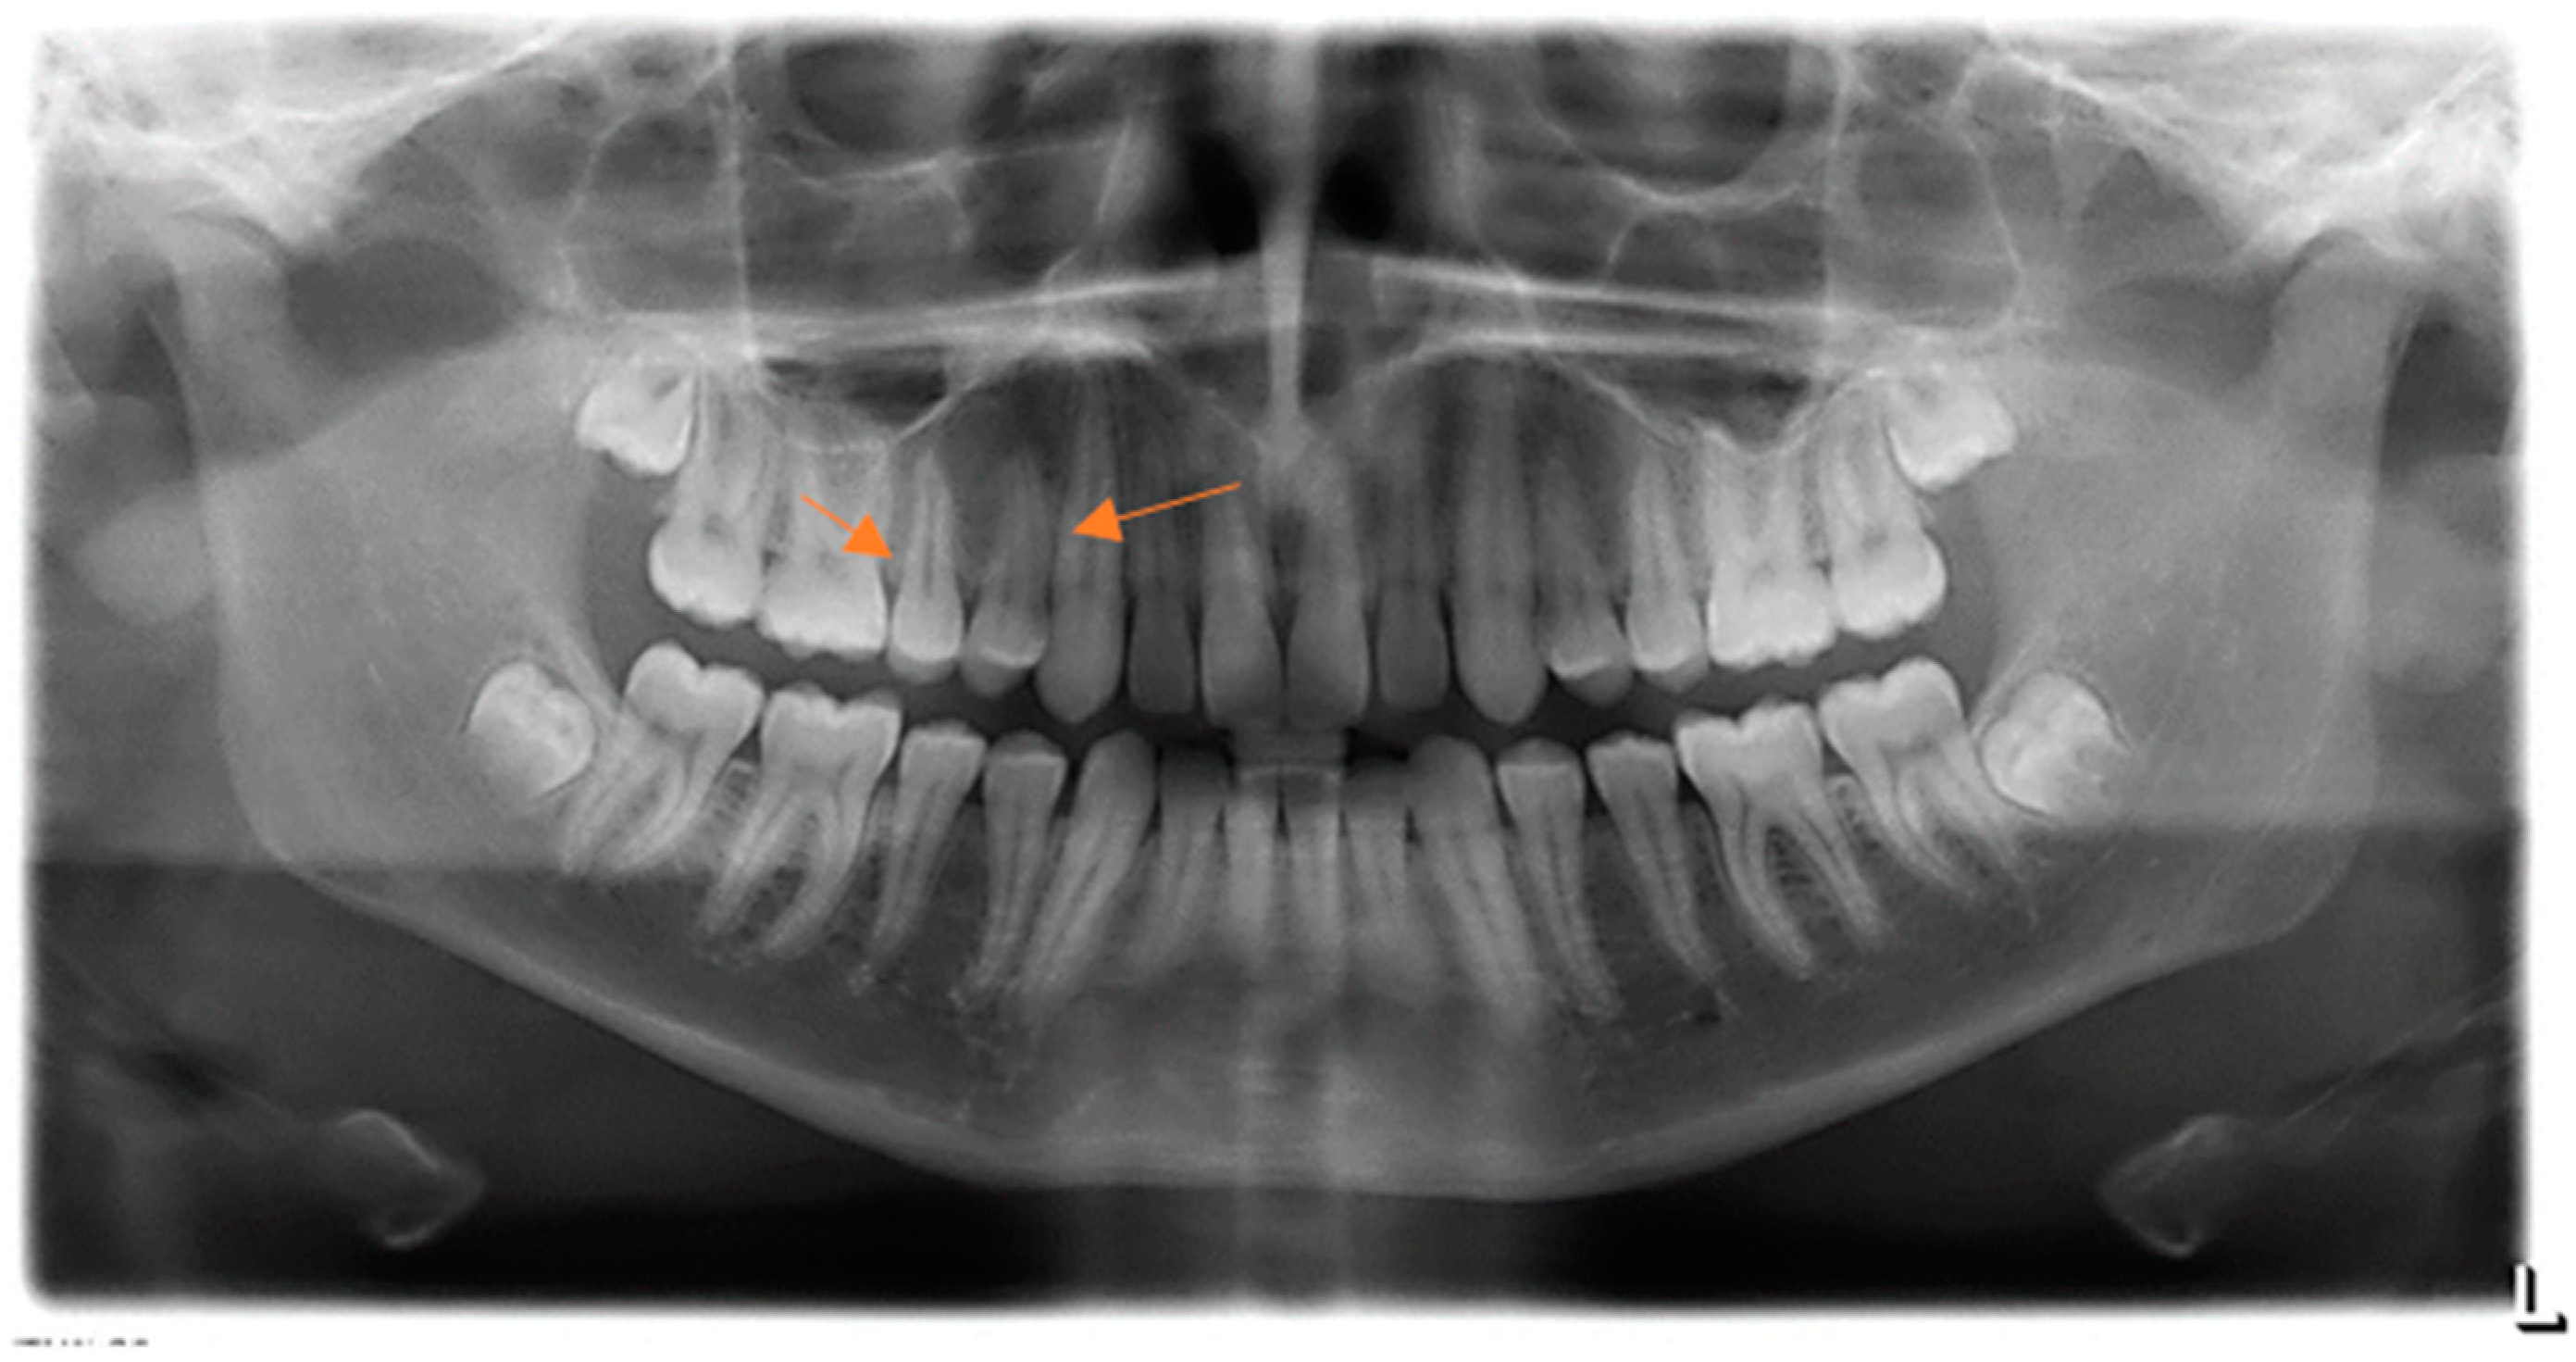

2. Case Presentation